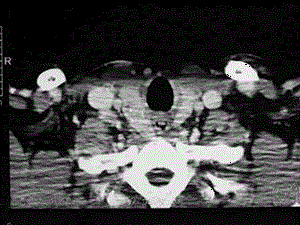

问题 患者,女性,32岁,因发现颈部肿块一个月入院,入院查体:甲状腺2度肿大,右侧甲状腺可触及一圆形,质中直径约3.5厘米的肿块,无压痛,随吞咽上下活动,颈部没有触及肿大淋巴结,甲状腺吸碘试验提示冷结节。 颈部CT检查结果如下图,对于本患者的诊断,我们要首先考虑 ( )

选项 A、甲状腺癌 B、淋巴结 C、甲舌囊肿 D、高功能甲状腺瘤 E、结节性甲状腺肿

答案 A